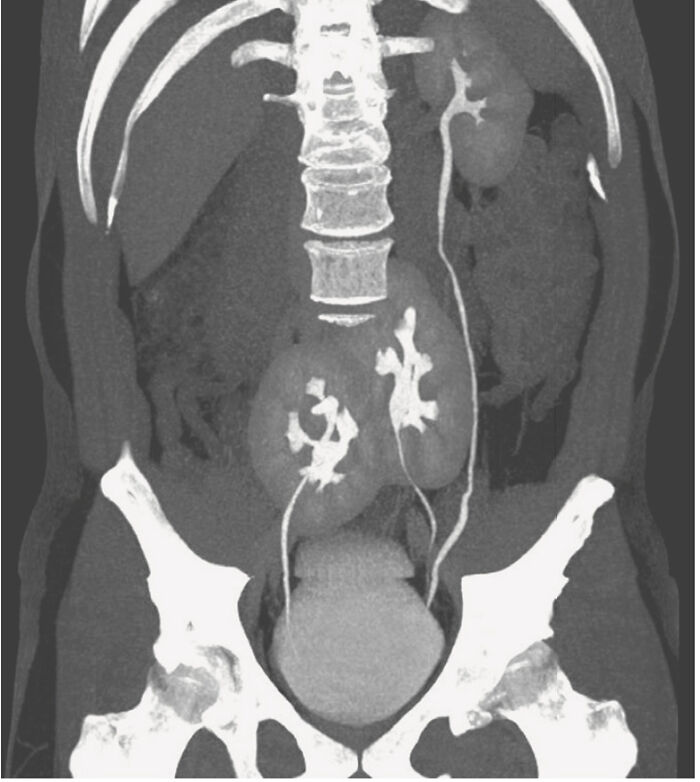

Three Kidneys Discovered In A Man! - Medical Case